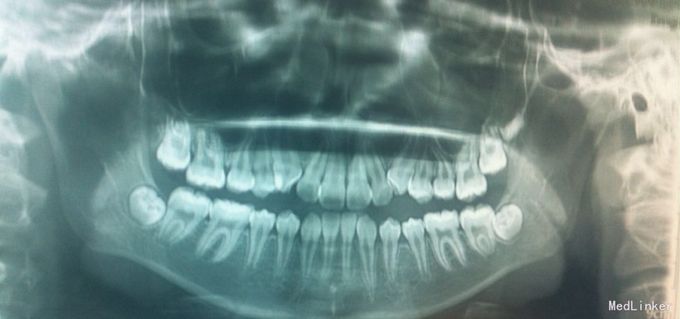

检查:恒牙期 右侧磨牙远中关系,左侧磨牙中性关系 前牙一度深覆合,正常覆盖 32、42未见 13、23唇侧错位 张口型异常 中线左偏约2mm 口腔卫生一般 X线未见32、42牙胚,28、38、48牙胚存在

诊断:安氏三类,先天缺牙 处理:拔牙矫治,直丝弓矫治器,拔除15、25,排齐整平上下牙列,关闭拔牙间隙,矫治后磨牙中性关系,前牙覆合覆盖正常,维持现有面型。

21牙X线示牙根较短,注意受力,防止松动脱落